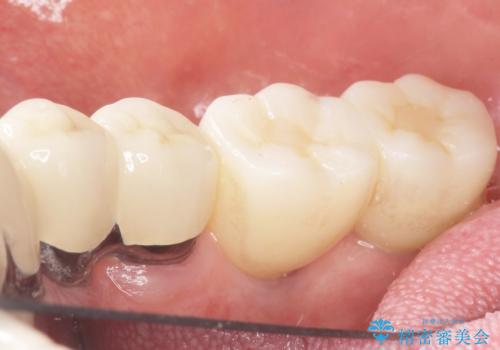

再生療法と骨外科処置により、歯周ポケットは全周2mm以下に改善されました。

保存が難しいと思われた歯を残すことができ、患者様にご満足頂けました。

歯周病治療と連結補綴により歯の動揺がなくなり、「なんでも食べられます!」と喜んで下さいました。

クラウンの種類:メタルボンドクラウン エコノミー